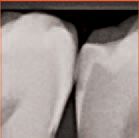

An interproximal lesion was noted on the bitewing on the distal proximal surface of tooth No. 29 (Figs. 3 and 4). The patient was informed of the diagnosis and his options for treatment, which ranged from monitoring the lesion over time to prepping and restoring in a traditional method. We also discussed with him a new technology that fills, reinforces and stabilizes demineralized enamel without removing healthy tooth structure and arrests the progress of the proximal lesion. The patient eagerly opted for the ICON infiltration concept.

An interproximal lesion was noted on the

bitewing on the distal proximal surface of tooth No.

29 (Fig. 3)

Digital x-ray of the lesion on tooth No. 29

(Fig. 4).

Figs. 11-12 Follow

up bitewing digital

x-rays at 7 months

and 12 months

shows the lesion

to be arrested and

not progressing

in dimension.